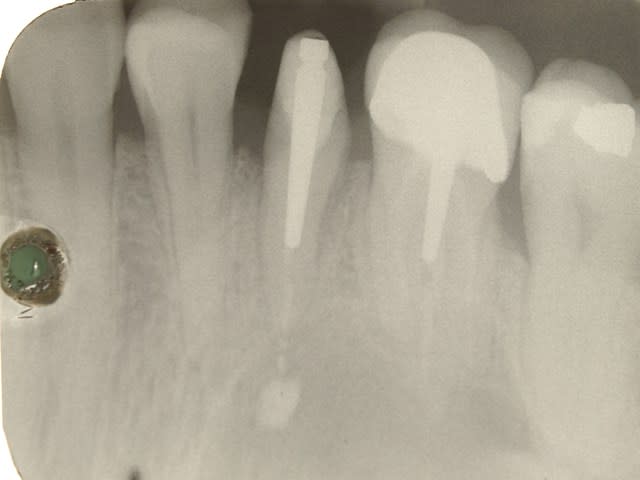

05/08/2014 à 11h37

ci joint la radio de controle du coup du loukoum :soit 1 an apres extraction reimplantation

http://www.eugenol.com/sujets/406035-1ere-fois-que-ca-m-arrive?page=32